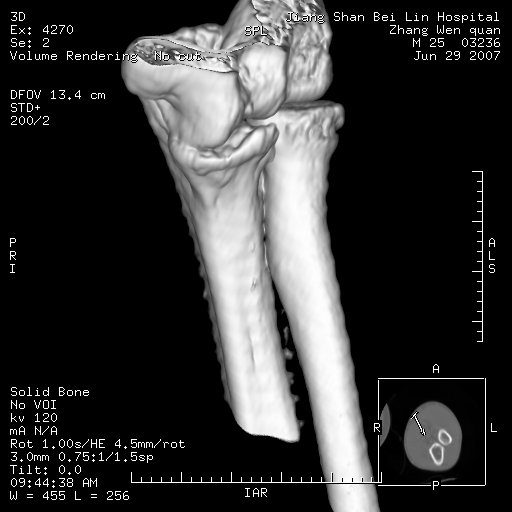

标题: CT8866:男27岁,正常吗?

患者男27岁,2007年3月查出患上肘关节滑膜结核,此后行手术滑膜剥除,今查ct

看一下上面的桡骨粗隆有问题吗?

桡骨粗隆有问题,术后改变

桡骨骨皮质破坏,结合病史考虑结核